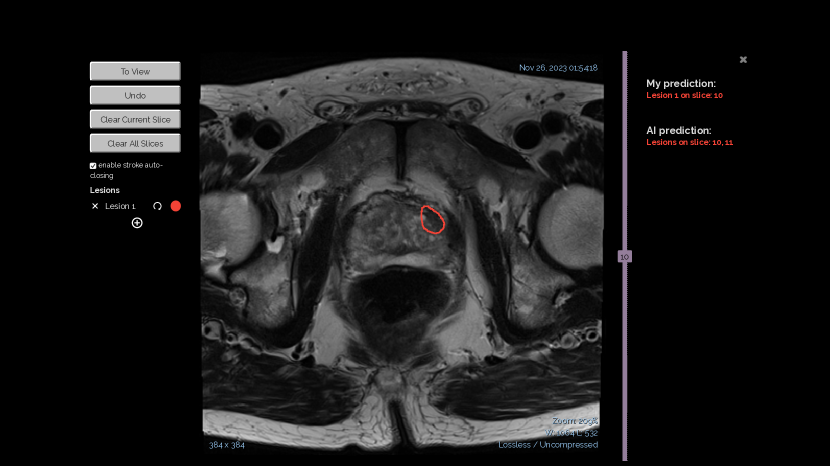

Refer to caption

(a) Patient case review interface.

(b) Lesion annotation panel.

(c) Performance feedback and attention check page.

Figure 2. Screenshots of the webapp interface for our human study. (a) Fig. 2(a) presents a user interface for patient case evaluation. An AI lesion prediction is highlighted with a red contour in the T2W sequence. On the right, the user’s current prediction is shown as “No Cancer,” and they are at the stage of evaluating the AI prediction to make a final diagnosis. (b) Fig. 2(b) shows the user interface of the Annotation Panel. The screenshot shows a current annotation of the user. The user can clear the annotation or add new annotations on the canvas. (c) Fig. 2(c) illustrates an example performance feedback page presented to a user before proceeding to Study 2. The page provides a summary of the total number of cases, including counts of correct and incorrect cases, the number of decision changes influenced by AI advice, and whether those changes were correct or incorrect. It also highlights key performance metrics such as accuracy, sensitivity, and specificity, derived from Study 1. To ensure users review the information carefully, they are required to answer attention check questions.

Study interface. Our study interface has three major components: the View Panel on the left, the Control Panel on the right, and the Annotation Panel as a pop-up in the center of the screen. The interface is shown in Fig. 2(a). In the View Panel, we display three image sequences (T2W, ADC, BWI) from the MRI scans of the current case. In the Control Panel, participants are informed about the current study (study 1 or 2) and provided with control buttons to make decisions or proceed to the next steps. Binary case-level AI predictions are also presented in this panel. Participants make their own predictions by clicking the buttons (‘Annotate Cancer” for positive cases and “No Cancer” for negative cases) and indicate their confidence level using a sliding bar. If a participant believes the case is positive, they click the ”Annotate Cancer” button, which triggers a pop-up window (Annotation Panel) displaying enlarged images from the T2W sequence of the current case, allowing participants to annotate the suspicious lesion areas. Participants can annotate any suspicious lesions by freely drawing on any image slice, using the sidebar to navigate between slices. The annotation interface is illustrated in Fig. 2(b).